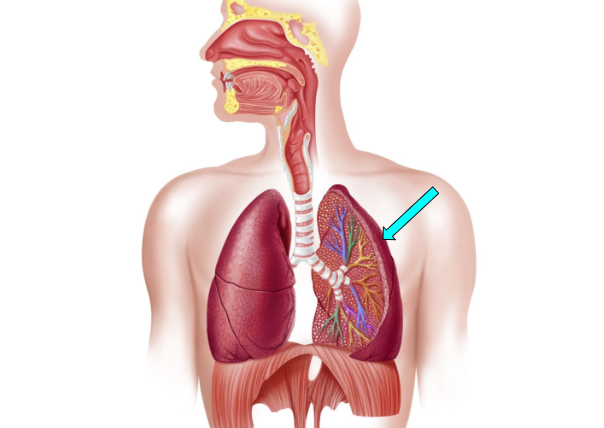

Alveoli

facilitate gas exchange through the lungs & bloods to exchange oxygen & carbon dioxide during respiration

Bronchioles

small airway that delivers oxygen to the alveoli for gas exchange

Bronchi

carry oxygen to and from the lungs

Right Lung (pic)

Bronchus (pic)

Bronchioles (pic)

Alveoli (pic)

Left Lung (pic)